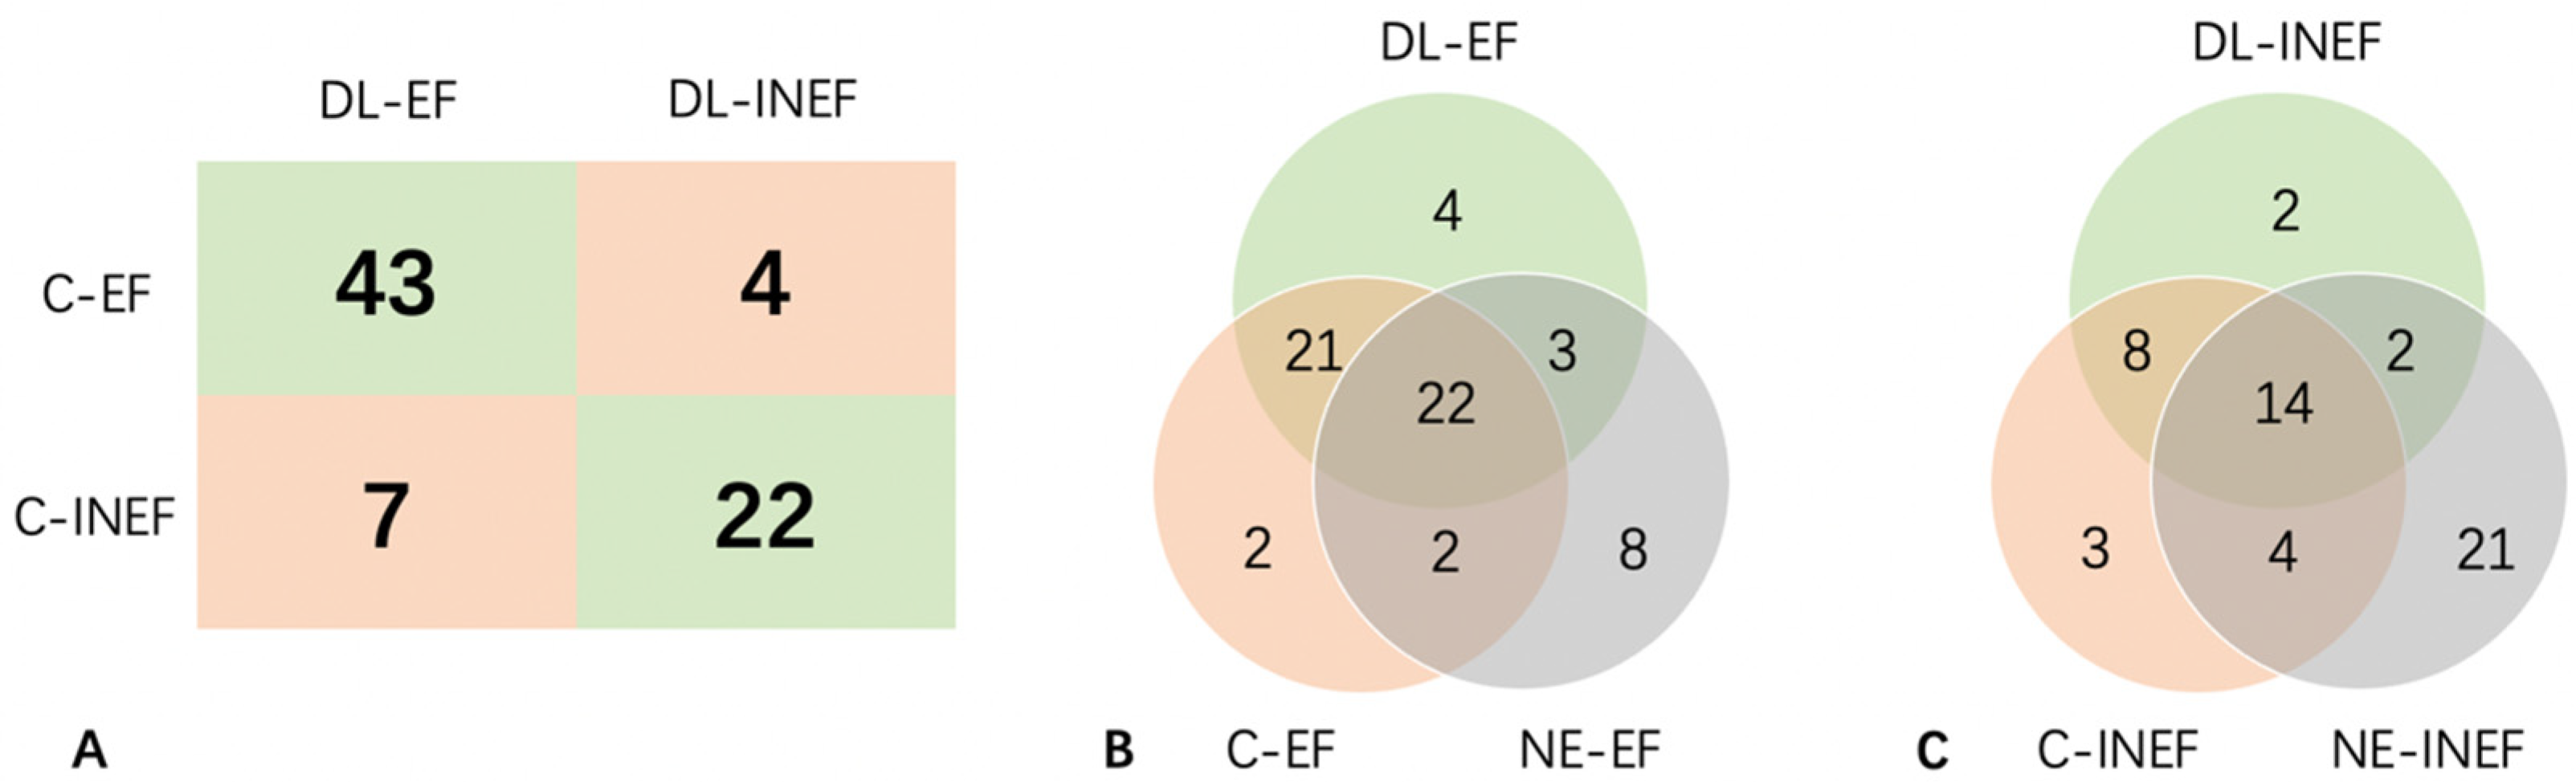

3.4. Prediction of Each Original Video by US+CEUS

3.5. Prediction of Each Original Video by CEUS-ROI